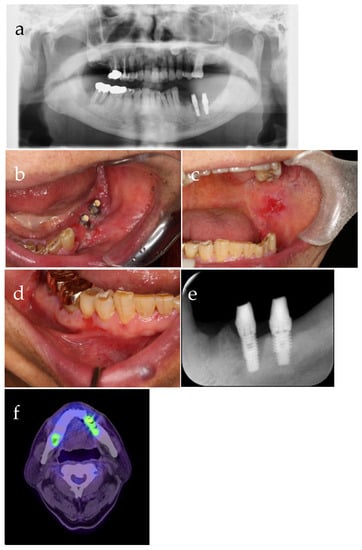

| 7 | (Figure 3) | Significant enlargement of the lesion due to bone melting at tooth 35 | ||

| 9 | Biopsy (Figure 4), | SBCWPV, OWS, NM (fourth) | ||

| HBO (20 times) | ||||

| 10 | Mandibular surgical anti-inflammatory surgery, removal of the implant in tooth 36, | PV, mandibular osteomyelitis/osteonecrosis, S/O: PIOSCC | SBCWPV, OWS, NM (fifth) | |

| HBO (10 times) | ||||

| 11 | Biopsy | White lesions from the mandibular wound | Keratinous material, NM (sixth) | |

| 12 | (Figure 5) | Pathological fracture | ||

| HBO (20 times), | ||||

| biopsy, | OWS, NM (seventh) | |||

| intermaxillary fixation | ||||

| 14 | Mandibular segmentectomy (Figure 6) | OWS, NM → Corrected to CC, pT4a (eighth) | ||

| 20 | Debridement Biopsy (Figure 7) | CC, PV | CC, pT4a (ninth) |